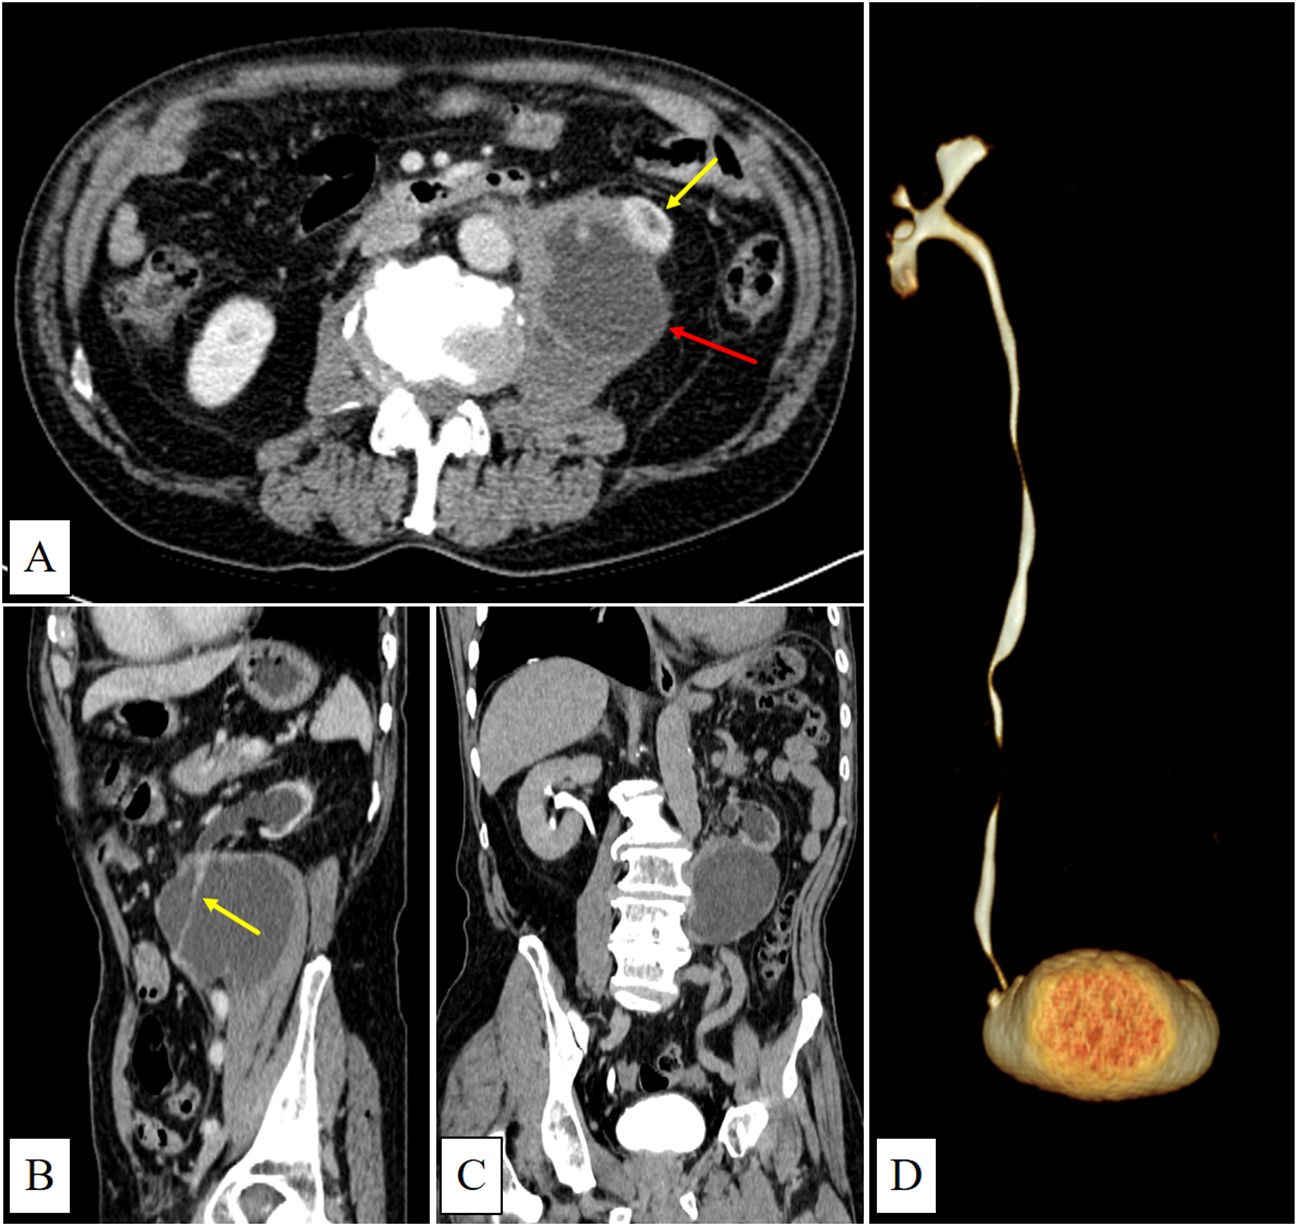

CT showed a large cystic-solid mass in the left retroperitoneal and psoas muscle region, with indistinct margins adjoining the left kidney. The left ureter was observed traversing the lesion. Additionally, the left kidney was atrophic with absent excretory function (Figures 1A–D).

CT scan images showing multiple views of an abdominal mass, highlighted with arrows in panels A, B, and C. Panel D displays a 3D reconstruction of the Urinary system.

Figure 1. (A) (venous phase) shows a predominantly cystic mass with irregular margins and mild enhancement located in the left psoas major region (red arrow). The lower pole of the left kidney is invaded (yellow arrow). (B) (sagittal view, venous phase) shows the left ureter running through the mass with mild enhancement(yellow arrow). (C) (delayed phase) demonstrates left renal atrophy, dilatation of the left renal pelvis and calyces, and absence of contrast filling within the mass. (D) (CTU) shows no contrast enhancement in the left renal pelvis, calyces, or ureter.